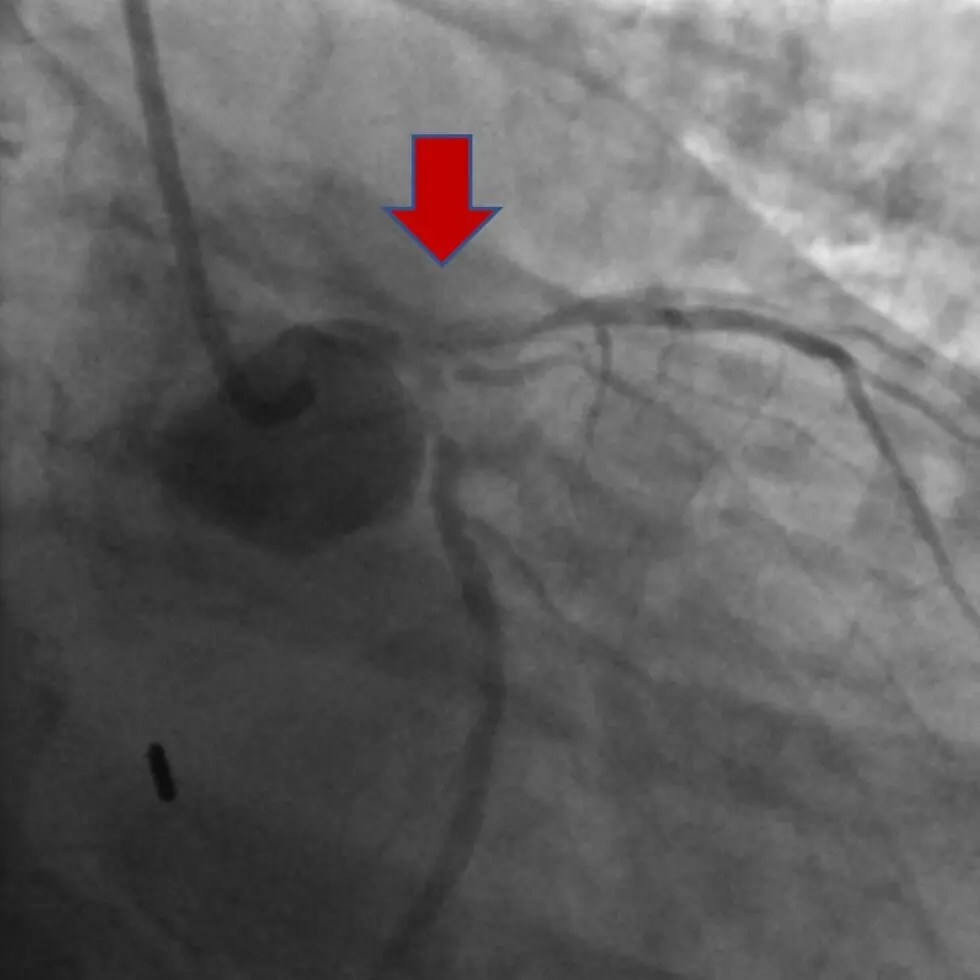

Primary Stenting of an Anomalous Left Anterior Descending Coronary

From www.ahajournals.org

Primary Stenting of an Anomalous Left Anterior Descending Coronary Jaw Pain After Heart Stent In case of recurring chest. Stents are typically used to treat angina and lower the risk of a heart attack. I had 4 stents placed in my heart.2 in november of. I had chest tightening and jaw pain and went to hospital. You may have heard the two go hand in hand. Jaw pain during a heart attack can be. Jaw Pain After Heart Stent.